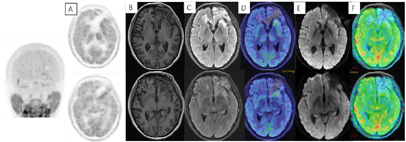

入院体格检查:T:36.8℃,P:69次/min,R:19次/min,BP:125/88 mmHg。专科体格检查:神志清楚,对答切题。双侧瞳孔等大等圆,直径约3 mm,对光反射灵敏。四肢肌力肌张力正常。生理反射存在,病理征阴性。既往无特殊病史。辅助检查:我院门诊MR示左额叶占位性病变(图2),倾向于高级别胶质瘤。

术后3周患者就诊于头颈肿瘤放化疗科,专科查体:左眼睑下垂,神清,言语清晰,伸舌居中,双侧瞳孔等大等圆,对光反射存在,四肢感觉活动可,肌力肌张力正常。2017年7月MR(图4)示左额叶术后改变伴出血,病灶内侧部分考虑肿瘤残留可能。为了更好地评估术后残留病变范围和制定放疗计划,患者行11C-MET PET/CT检查(图5A-D),结果示左侧脑室前角旁-左侧基底节区团块状稍高密度影,蛋氨酸代谢异常增高,考虑肿瘤残留。参照2016 ESTRO-ACROP指南[1],继发性胶质母细胞瘤放疗GTV靶区需包含术腔、T1增强上的强化区域及T2 FLAIR上的高信号区域,术后PET/CT显像所示的氨基酸代谢活跃病灶被包含在GTV之内(图5E)。患者于2017年7月始行左额叶病灶放疗(PTV 60Gy/30F,同步口服替莫唑胺化疗75mg/m2,qd)。结束后复查PET/CT(图5F-I)示病变范围明显缩小,代谢程度较前减低,左额叶少许病变存活,遂对残留病灶局部放疗加量(GTV如图5J,6Gy/3F)。放疗过程顺利,期间出现Ⅲ°白细胞减低,予以升白细胞治疗后好转出院。后于2017年10月起口服替莫唑胺辅助化疗(150~200mg/m2,d1-d5,q28d),期间规律复查。